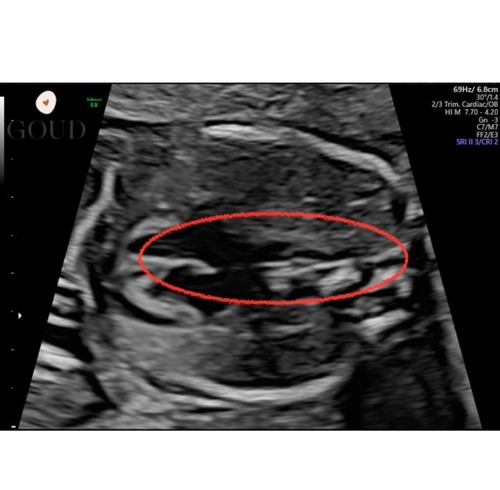

Ik had afgelopen maandag de 20 weken echo en daar zagen ze een soort overslag in het hartritme. Dit was echt duidelijk te zien, voor ons ook, en was niet normaal. We zaten direct ongelofelijk in de stress en waren echt verslagen.

Dinsdagochtend kregen we gelukkig direct een guo in het umcg: helemaal niks aan de hand. De arts heeft mega lang naar het hartje gekeken, het hele kindje opnieuw van onder tot boven gecheckt: niks te zien. De overslag was er niet meer. 24 uur verschil..

Hij gaf aan dat het met dit termijn vaak onrijpheid is van het hartje, én dat je dit zomaar volgende week wel weer kan zien, en daarna niet meer. Volgens mij zelfs tot 36 weken.